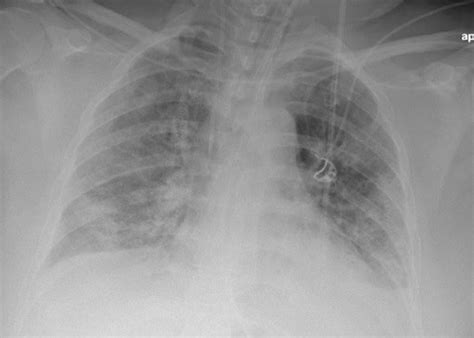

The Pulmonary Embolism X Ray plays a crucial role in the initial evaluation of suspected PE. While it cannot definitively diagnose PE, it can help rule out other conditions that may present with similar symptoms, such as pneumonia, heart failure, or lung cancer. A normal chest X-ray does not exclude the possibility of PE, but it can provide valuable information that guides further diagnostic testing.

Key findings on a Pulmonary Embolism X Ray that may suggest PE include:

• Wedge-shaped opacities: These are areas of increased density in the lung tissue, often seen in the periphery of the lung.

• Pleural effusion: Fluid accumulation in the pleural space, which can be a sign of inflammation or infection.

• Enlarged pulmonary arteries: Dilatation of the pulmonary arteries, which may indicate increased pressure due to a clot.

• Atelectasis: Collapse or incomplete expansion of the lung tissue, which can be a sign of obstruction.

However, it is important to note that these findings are not specific to PE and can be seen in other conditions. Therefore, further diagnostic testing is often required to confirm the diagnosis.